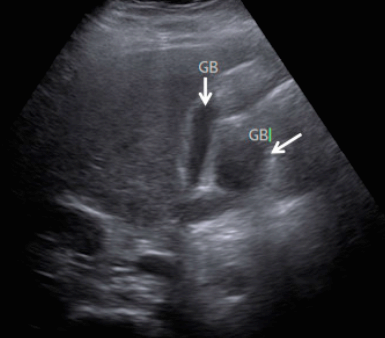

4) Double GB

기저부와 담낭관 부위가 2개인 담낭이다. 각각 cystic duct를 가진다.

5) Duplicated GB

Double GB 와의 차이점은 하나의 cystic duct를 가진다.